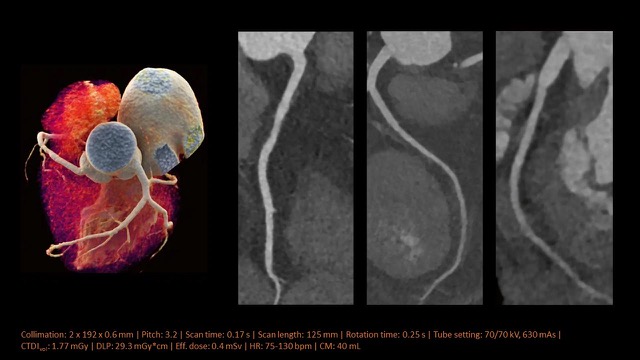

La Cardio TC con SOMATOM Force (Siemens Healthineers) rappresenta l’avanguardia nell’imaging cardiaco non invasivo. Utilizza una tecnologia a doppia sorgente (Dual Source) di terza generazione per ottenere immagini ad alta risoluzione in frazioni di secondo, riducendo drasticamente le radiazioni e il mezzo di contrasto. Permette esami rapidi su pazienti con frequenza cardiaca alta/instabile, obesità o che non trattengono il respiro, ideale per lo studio delle coronarie, bypass e stent.

- Velocità e Risoluzione: La tecnologia Dual Source (due tubi e due detettori) permette di coprire l’intero cuore in meno di un secondo, riducendo gli artefatti da movimento.

- Basso Dosaggio (Low Dose): Consente indagini con una esposizione alle radiazioni molto ridotta, spesso inferiore a 1 mSv, aumentando la sicurezza per il paziente.